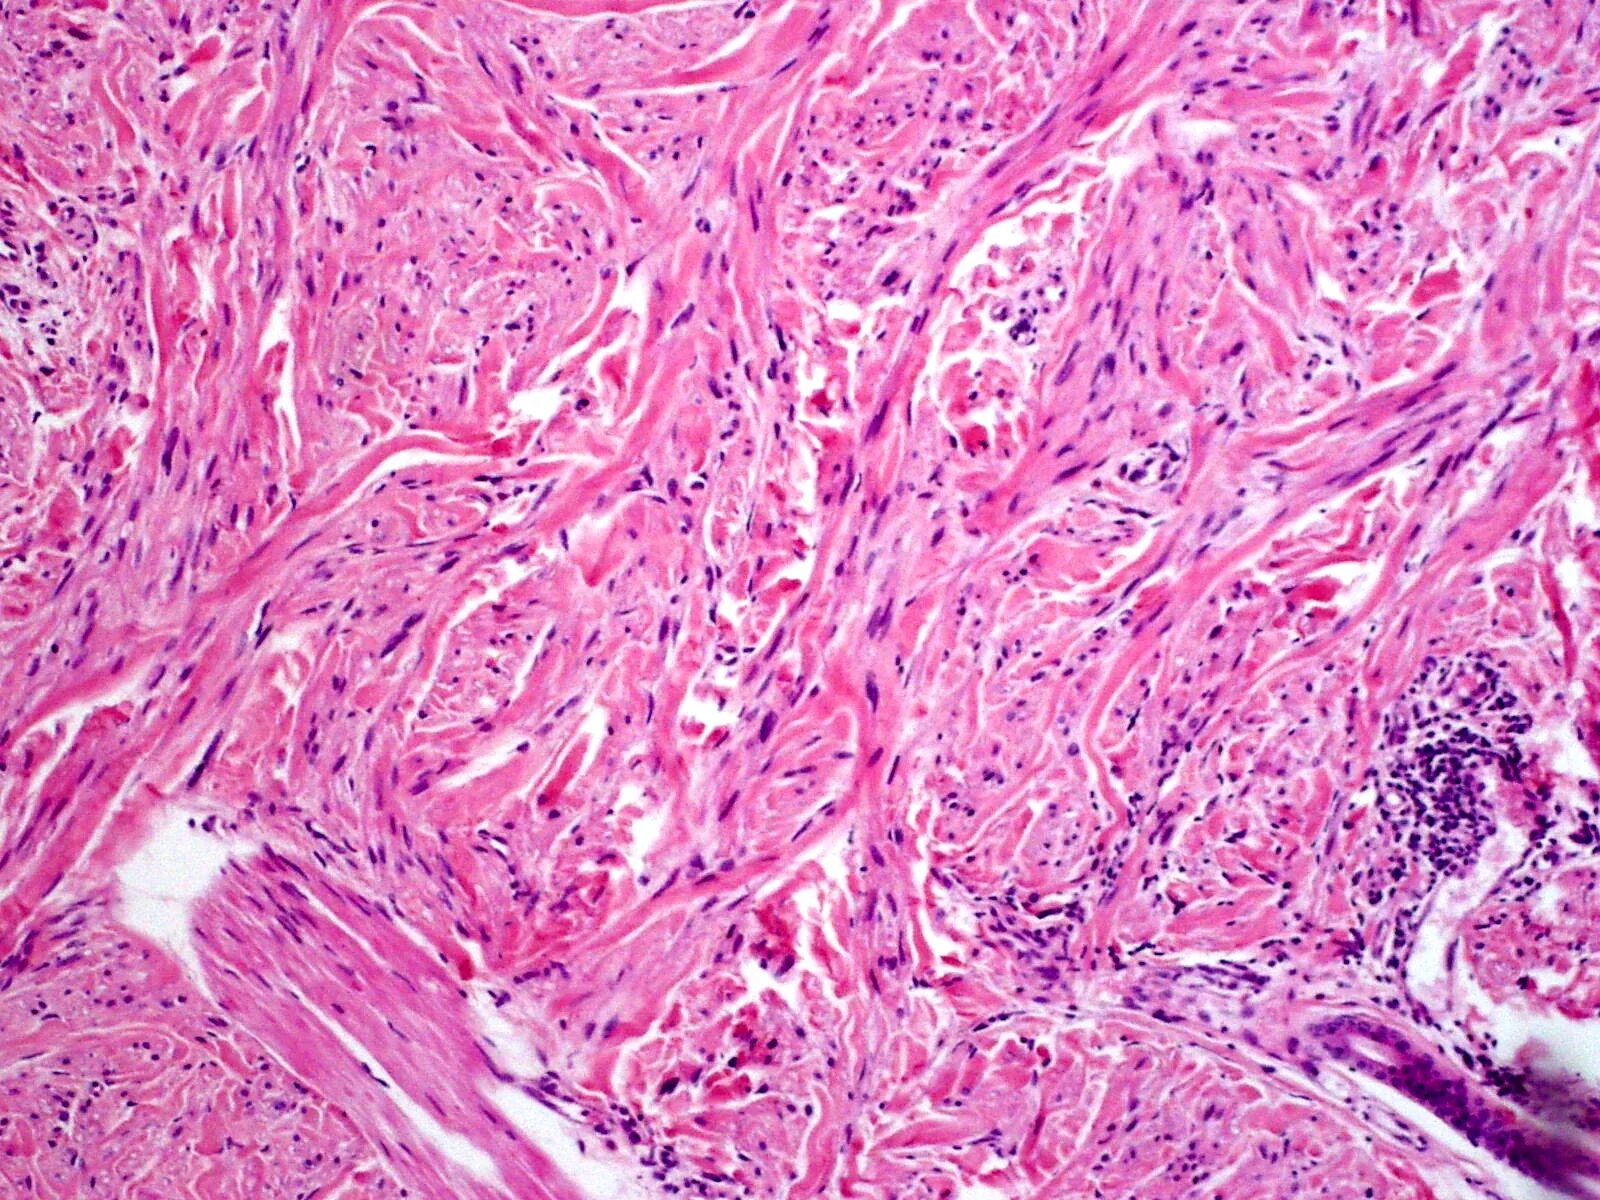

Инфильтрация в гистологии